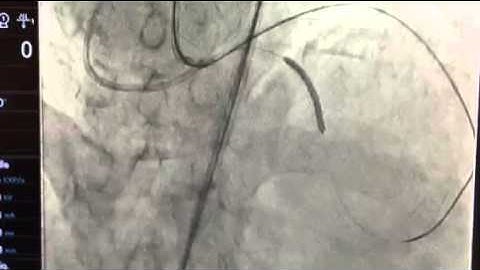

Retrograde LCX CTO PCI Through Venous Graft By Dr. Sharath Reddy